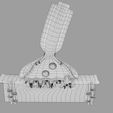

神经肌肉接头示意图